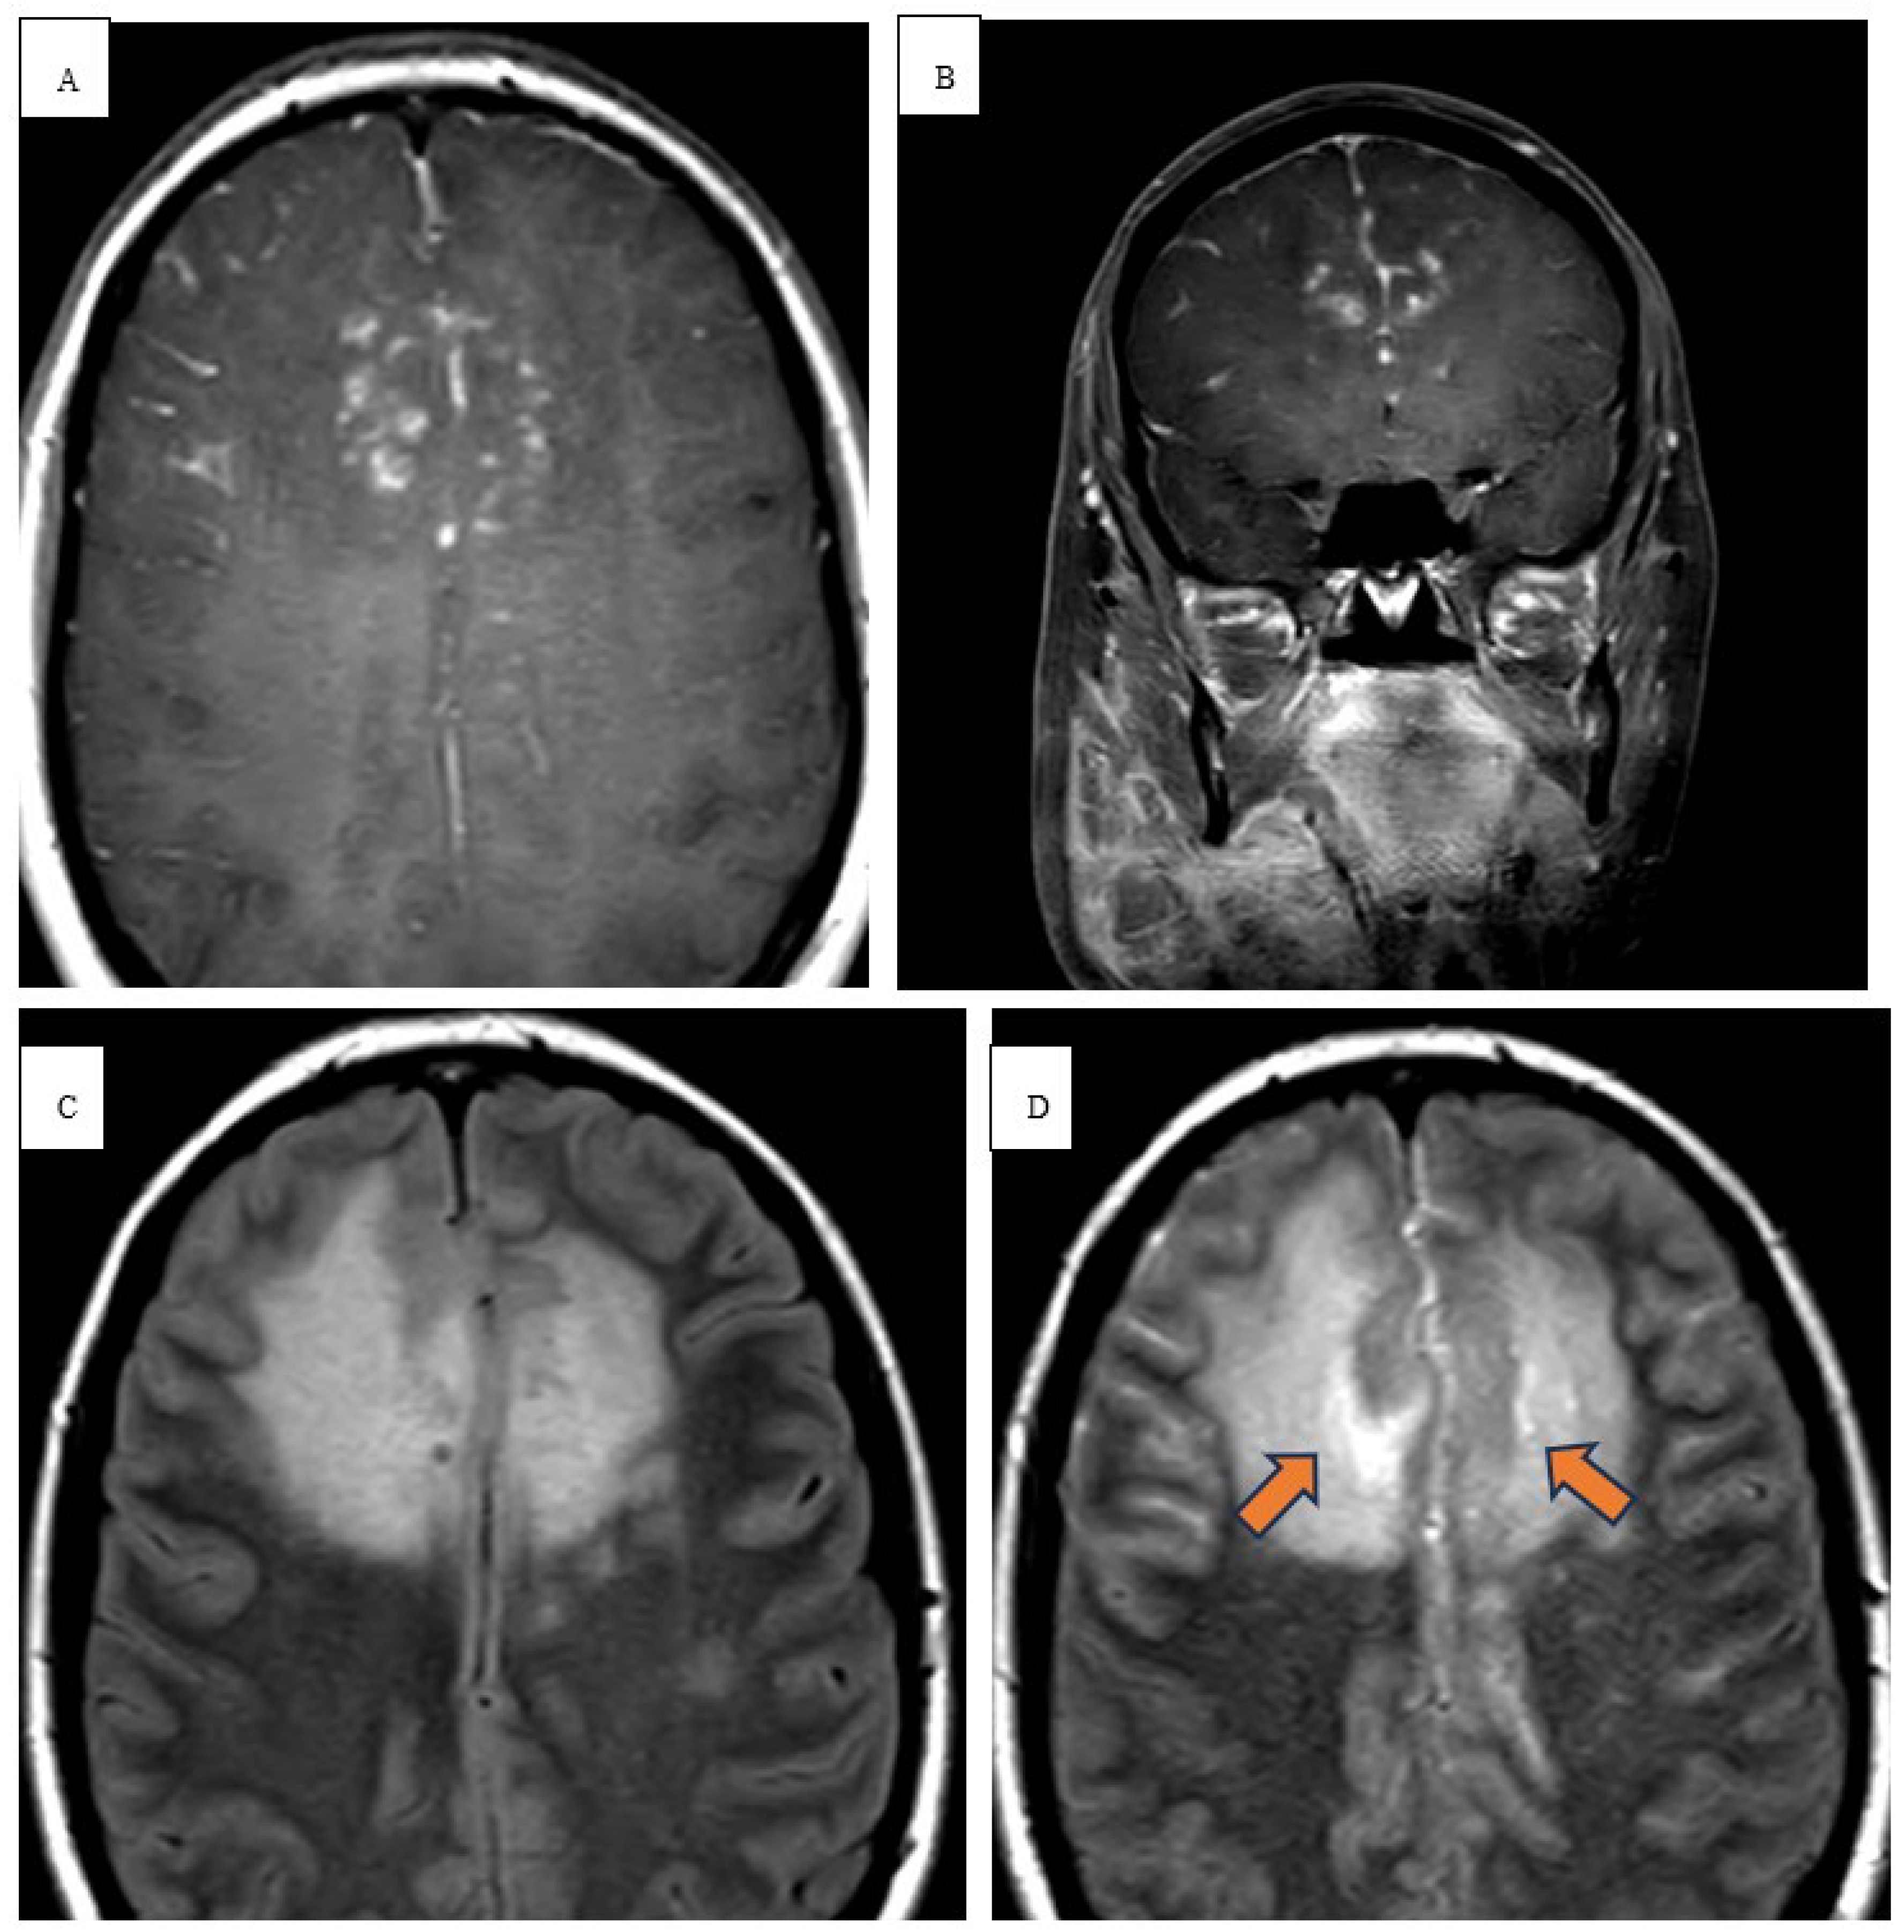

Thirty-one-year-old male with a history of untreated Mycobacterium nucogenicum isolated on bronchoscopy and bronchoalveolar lavage (BAL) culture 6 months prior, stage 4b mixed cellularity cHL. He was deemed asymptomatic from the mycobacterium infection, subsequent excisional lymph node biopsy confirmed the diagnosis, and the decision was made to start first line A-AVD regimen. The patient received 3 cycles with clinical improvement of his constitution symptoms. However, he subsequently presented to the hospital with 3-day onset of ataxia. He sustained a total of 3 falls with severe frontal headache that he rates as a 9/10 in severity. He denied loss of consciousness, problems with his vision, positional worsening, prior history of headaches, and neck pain. He reported worsening gait and generalized weakness over the last few days. Vital signs on admission were significant: 38.2C, 101 beats/min, and BP 113/52 mmHg. He developed intermittent fevers as high as 39.4C throughout his hospital course. Physical exam revealed abnormal finger to nose and heel to shin testing with broad based magnetic gait and impaired tandem gait. Labs revealed white blood cells (WBCs) 1.65x10(3)/mcL with absolute neutrophil count of 1.02x10(3)/mcL, ALP 100 u/L, ALT 75 u/L, AST 118 u/L. Lumbar puncture with cerebrospinal fluid (CSF) analysis did not indicate evidence of meningitis. Serology was positive for John Cunningham (JC) virus, cytomegalovirus (CMV), Ebstein Barr virus (EBV) but the CSF was negative for JC virus, CMV and herpes simplex virus (HSV). NCCT demonstrated vasogenic edema within the right temporal lobe. MRI brain with and without contrast revealed spherical 1.0 x 1.0 x 1.1 cm lesion that increased in size to 2.4 x 2.1 x 2.2 cm in 3 weeks (Figure 1 and Figure 2). Patient underwent a right pteronial craniotomy with stereotactic right temporal tip dural mass biopsy by neurosurgery. Histopathology confirmed cHL of the brain with reactive gliosis of the brain parenchyma. He was initiated on a dexamethasone taper over 5 days and salvage therapy with DHAP as inpatient and eventually immunotherapy with pembrolizumab with gemcitabine, vinorelbine, and liposomal doxorubicin (pembro-GVD) as outpatient. Repeat positron emission tomography (PET) CT scan demonstrated positive response and MRI of brain negative for recurrence of disease. Subsequently, the patient had progressive disease after 3 lines of therapy and deem stem cell transplant ineligible eventually transitioned to hospice and end of life care.

Radiologically, the first-line imaging modality should be a NCCT scan [14,15]. Characteristic findings include a hyperattenuating lesion associated with edema, while immunocompromised patients may have a more heterogenous or even hypoattenuating appearance [14]. MRI reveals iso- to hypointense lesion(s) on T1 weighted scans and iso- to hyperintensity on T2 weighted images [16]. DWI in immunocompetent patients show strong restricted diffusion with low ADC, however, lymphomatous spread in immunocompromised patients is more heterogenous with scattered lesions [17]. In high grade tumors and other metastatic tumors, there is high ADC due to significant vasogenic edema [15]. Our immunocompromised patient in case 1 revealed peripheral restricted diffusion on DWI with T1 isotensity, T2/FLAIR central hyperintensity, and peripheral T2/FLAIR hypotensity (Figure 1 and Figure 2). In a similar sense, case 2 demonstrated restricted diffusion on DWI and low ADC (Figure 3).

Figure 2. Pre-T2 axial (A) and Post-T2 axial (B) contrast FLAIR images demonstrating anterior pachymeningeal enhancement, central hyperintensity, and peripheral hypointensity (blue arrow). Pretreatment MR imaging of brain with sb1000 (C) with enhancement (D).